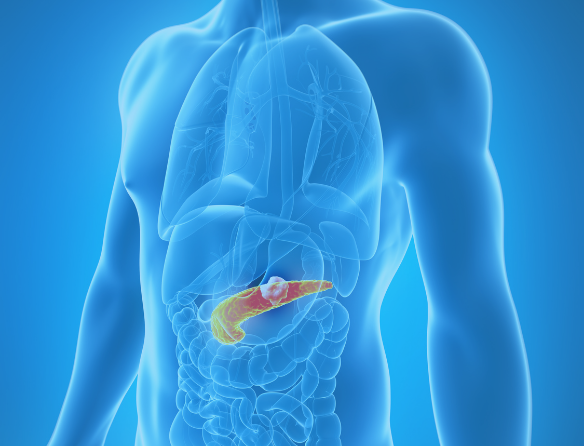

Metastasis – when cancer cells spread from the tissue of origin to other parts of the body – is the most deadly attribute of cancers and is responsible for more than 90% of deaths and loss of quality of life. A better understanding of metastasis is required so that physicians can intervene and save lives of cancer patients.

This two-pronged approach will permit Dr. Welch to not only develop novel metastatic cancer markers to assess a patient’s likelihood of developing metastasis, but also to develop unique anti-metastasis therapies. His current research regarding cancer metastasis has high impact for patients with breast, lung, ovarian, pancreatic, prostate, kidney and skin cancer.